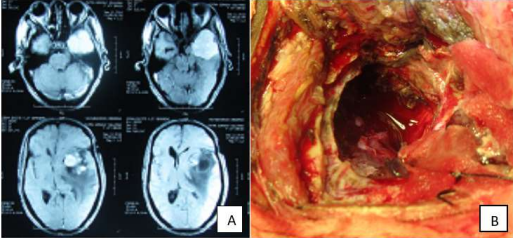

Thirty two years old house wife, from eastern region of the Sudan, presented complaining of headache and impaired vision of the right eye, which is gradually progressive over 10 years duration.

On examination she looked well generally, fully conscious, oriented, had finger clubbing, normal left eye but diminished vision of the right eye with no motor deficits.

MRI of the brain showed right tuberculum sellae tumor she was operated through right subfrontal craniotomy. The tumor was totally resected, the patient showed gradual post-operative improvement till full recovery of the vision of the right eye within 6 months.

Histopathology revealed grade1 meninigioma.

Image (A)and (B) are the preoperative MRI of case no(5) showing the tumor, Image (C) is an operative image showing tumor resction cavity

Image (D) is post-operative MRI showing complete resection of the tumor, Image (E) is the patient after complete recovery 3 months post-operatively.